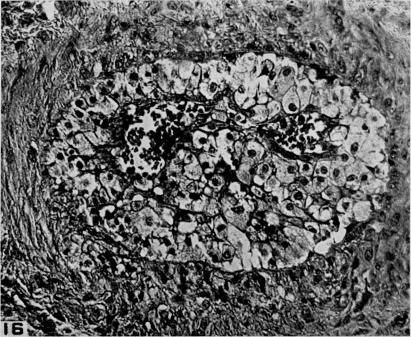

Studies on the pathogenesis of vascular disease; the effect of intravenous egg-yolk emulsions on inflammatory lesions of the aorta and coronary arteries of dogs.

Yale J Biol Med. 1956 Sep;29(1):9-22.